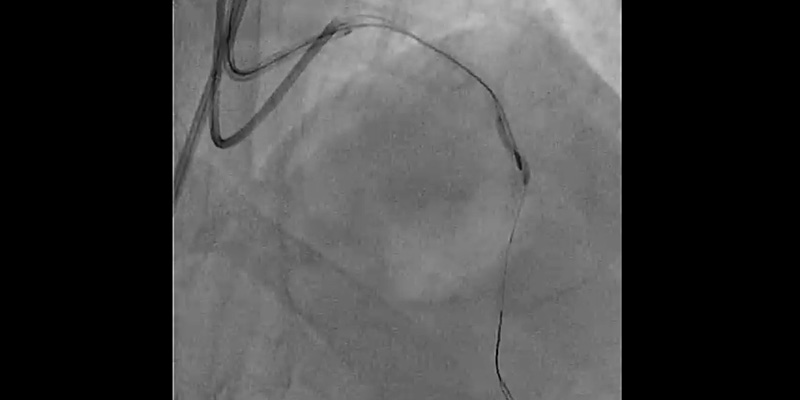

• Femoral access: 7 Fr. EBU4 7F Guiding catheter.

• The LAD was first wired with a hydrophilic wire and then exchanged for the Rotawire™ Extra Support guide wire using a microcatheter.

• Rotational atherectomy with a 1.25mm burr: A 1.25 mm burr was selected due to the severity of the stenosis and calcium. Individual rotablation runs (30-45 sec) were done with a burr speed of 165,000 rpm

• Due to severe calcification and vessel angulation, the burr jumped distal to the lesion even with a gentle manipulation of the system. Withdrawal of the burr was unsuccessful. The system was put into Dynaglide which also resulted in an unsuccessful retrieval attempt. A hydrophilic guidewire was placed parallel to the RotablatorTM catheter but a balloon could not pass through the 7Fr femoral guiding catheter.

• Complication management strategy: A “Ping-Pong” technique was performed. The LM was engaged with a 6F radial EBU guiding catheter, while pulling back the 7Fr catheter a few centimetres. A hydrophilic wire was placed in the distal LAD parallel to the rotablator catheter and sequential dilatations with 1.2mm and 2.0mm balloons were performed at the site where the burr was trapped. This dislodged the burr, allowing it to be easily withdrawn.